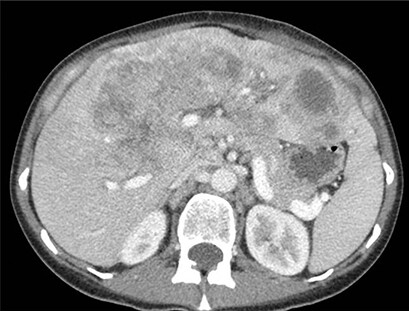

En tidligere frisk lite-røykende kvinne i 30-årene oppsøkte lege fordi hun følte seg sliten og hadde smerter i øvre del av buken. Hun ble utredet med blant annet CT abdomen, som viste multiple metastasesuspekte lesjoner opptil 12 cm i diameter i lever og forstørrede lymfeknuter i abdomen (figur 1a). Biopsi fra lever viste adenokarsinom. MR lever sannsynliggjorde diagnosen kolangiokarsinom med affeksjon av nesten alle leversegmenter.

CT-bilder tatt etter fem ukers behandling med entrektinib viste tydelig respons. Store konfluerende tumormasser sentralt i leveren var minket til 9,8 cm fra 11,7 cm før start av entrektinib, og en metastase i venstre leverlapp hadde blitt redusert fra 7,2 cm til 4,9 cm (figur 1b). Det var også tilbakegang av ascites.